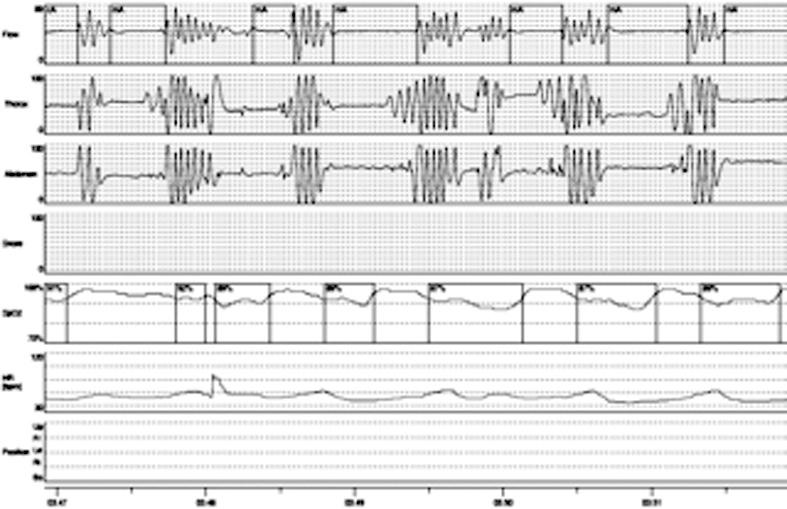

Patients affected by glycogenosis type II frequently present sleep disordered breathing. The presence of symptoms suggestive of sleep breathing disorders was investigated, by a questionnaire, in 10 patients, affected by adult or juvenile forms of glycogenosis type II. Diurnal respiratory function, diaphragm weakness and nocturnal respiratory pattern were evaluated at the enrolment. In patients presenting sleep disordered breathing, the same parameters were re-evaluated after treatment with assisted non invasive ventilation. Out of 10 patients, 5 presented symptoms suggestive of sleep-disordered breathing at the baseline, 2 a pattern of sleep apnea syndrome and 3 nocturnal hypoventilation. All patients presented diaphragmatic weakness. No correlation was found between forced vital capacity values (FVC) in sit position and nocturnal respiratory disorders. Five patients with respiratory disorders were treated with non invasive ventilation. All patients - after one month of treatment - showed an improvement in symptoms with reduced diurnal hypersomnia (ESS < 10), absence of morning headaches and nocturnal awakenings, and reduced nicturia regardless the modality of ventilation. We recommend that all patients with glycogenosis type II, once diagnosed, are carefully monitored for the development of respiratory involvement, even in the absence of reduced FVC values and in the early stages of the disease, to receive appropriate therapy.

II型糖原贮积病患者常出现睡眠呼吸障碍。通过问卷调查,对10例成年或青少年型II型糖原贮积病患者进行了睡眠呼吸障碍相关症状的调查。入组时评估了日间呼吸功能、膈肌无力和夜间呼吸模式。对于存在睡眠呼吸障碍的患者,在接受无创通气治疗后重新评估相同参数。10例患者中,5例在基线时出现睡眠呼吸障碍相关症状,2例为睡眠呼吸暂停综合征模式,3例为夜间通气不足。所有患者均存在膈肌无力。坐位时的用力肺活量(FVC)值与夜间呼吸障碍之间未发现相关性。5例呼吸障碍患者接受了无创通气治疗。所有患者在治疗1个月后症状均有改善,日间过度嗜睡减少(Epworth嗜睡量表评分<10),无晨起头痛和夜间觉醒,夜尿减少,且与通气方式无关。我们建议,所有II型糖原贮积病患者一旦确诊,即使在FVC值未降低且疾病早期阶段,也应密切监测呼吸受累情况,以便接受适当治疗。